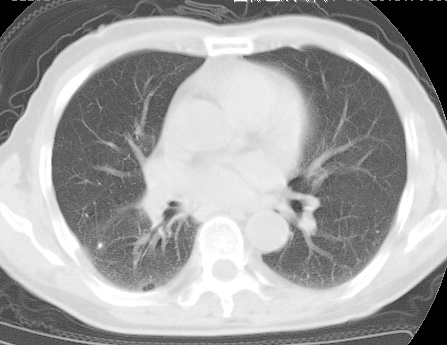

标题: CT24032:男65岁,咳嗽,吸烟20余年,无发热,咳痰 [打印本页]

标题: CT24032:男65岁,咳嗽,吸烟20余年,无发热,咳痰

考虑右肺中叶不张,请大家发表意见

右肺中叶不张、肺门轮廓增大,占位不除外;建议增强,必要时支气管镜详查。

右肺中叶支气管闭塞,中叶肺不张,右侧肺门见肿块影。中心型肺癌的可能大。建议支气管镜检查。

右中叶体积明显缩小,且其支气管未显示,先考虑:中心型肺癌班右中叶肺不张。

建议:支气管镜检查。

考虑右肺中叶中央型肺癌并右肺中叶肺不张;建议:行纤支镜检查。

右肺门旁类圆形肿块影,右肺中叶不张,建议纤支镜检查。

1右肺门旁类圆形肿块影,右肺中叶不张,建议纤支镜检查

2右侧胸膜增厚,右侧叶间胸膜区钙化

3右肺下叶小囊状透亮影考虑肺气肿